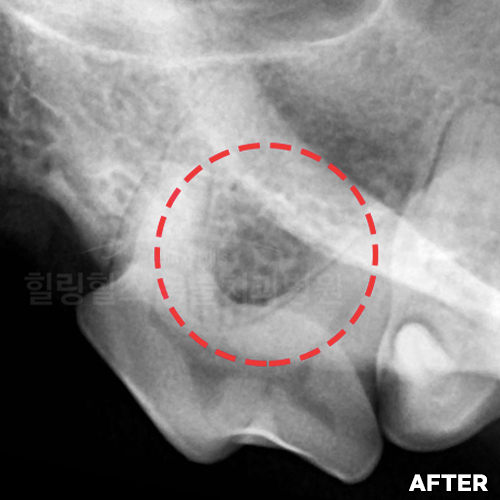

[치주염 치료 후 자라난 잇몸뼈]